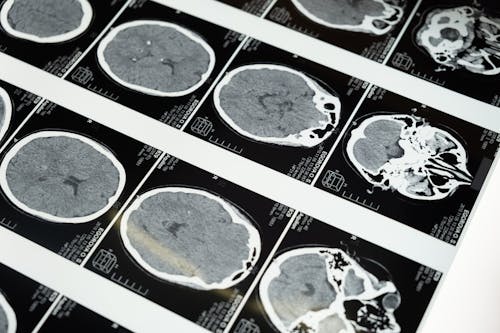

- 외상성 뇌 손상: 교통사고, 낙상, 폭행 등

- 뇌졸중 또는 뇌출혈